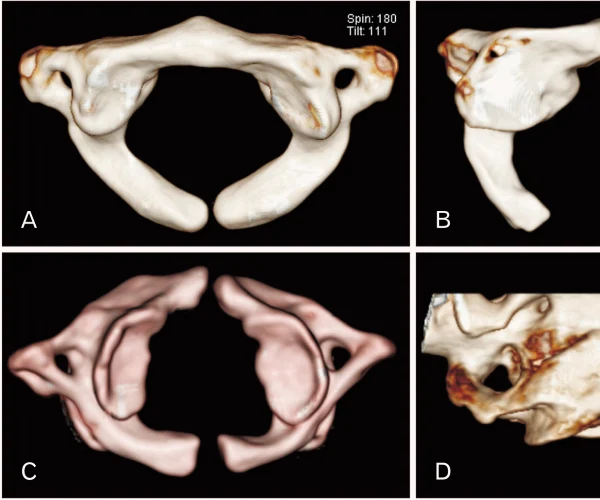

CT Showing Diastem

Bony Diaster

Split Cord Syndrome